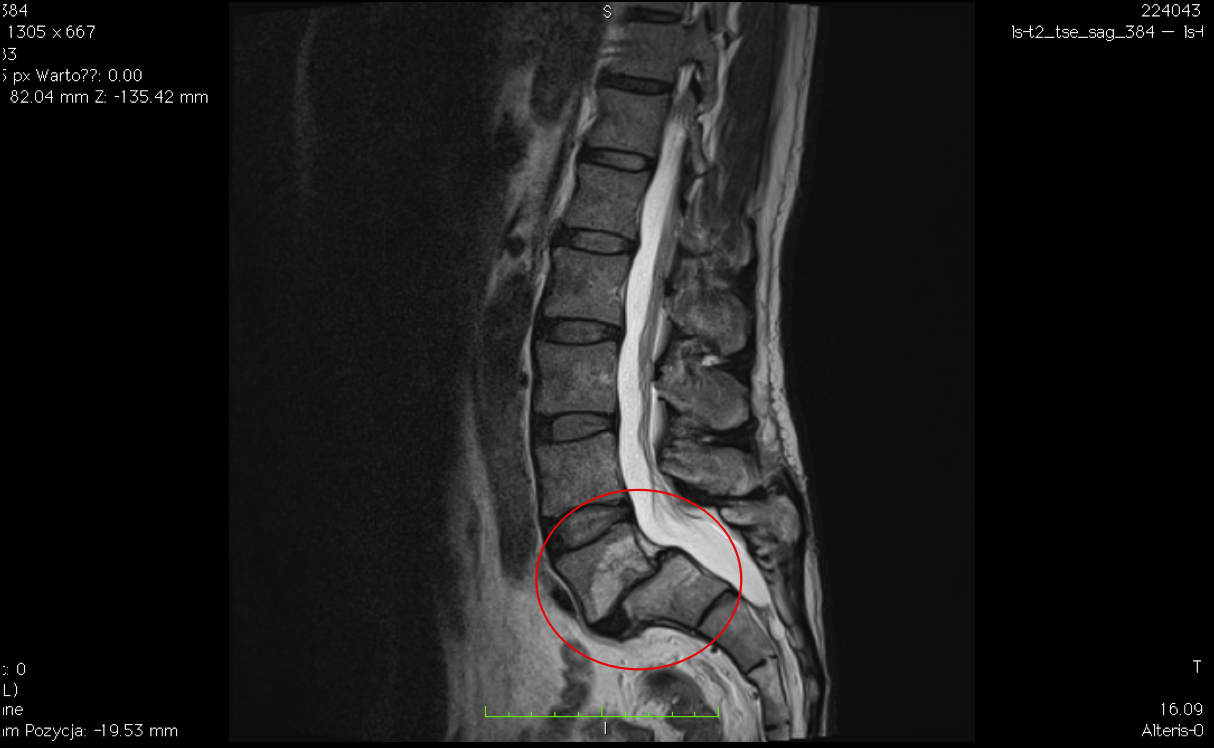

Bardzo zaawansowany strukturalnie kręgozmyk L5-S1 (II/III stopień), dający pacjentowi niewielkie dolegliwości bólowe oraz znikome objawy neurologiczne.